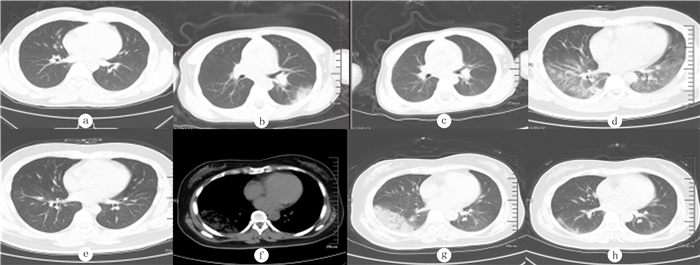

1.4 影像学检查所有病人均进行CT扫描。设备采用飞利浦16排螺旋CT;病人均采取仰卧位, 扫描范围从胸廓入口至双侧肋弓下缘; 扫描参数为:120 kV, 100~200 mA。根据疾病发展的影像学特点,将肺部影像学表现分为4期:1期无明显肺部阴影;2期仅存在多发小斑片影及间质改变,肺外带明显;3期存在双肺多发磨玻璃影、浸润影,无肺实变;4期在3期基础上出现肺实变。多发:指病灶分布在两个以上肺段(含两个肺段)。每例病人肺部影像分期以其肺部病变影像进展的最高峰判定[5]。各期典型CT影像特征及转归见图 1。

| a:1期,无明显肺部阴影;b:2期,仅存在多发小斑片状影及间质改变,肺外带明显;d:3期,存在双肺多发磨玻璃影、浸润影,无肺实变;f、g:4期,存在肺实变;c、e、h:治疗后影像,病灶明显吸收。 图 1 COVID-19病人各期治疗前后胸部CT影像 |